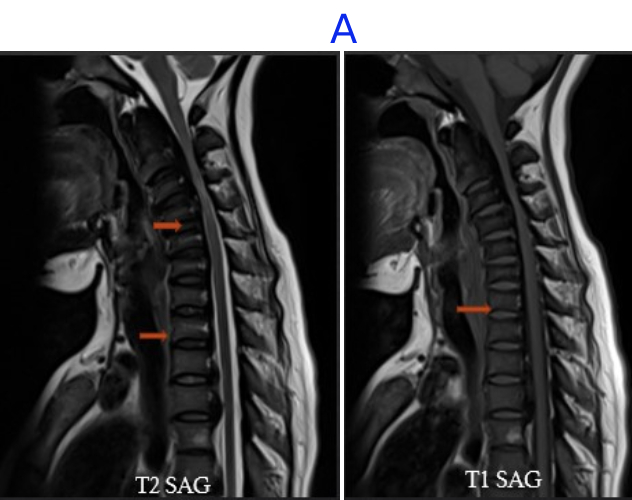

A) LEGENDS

• Vertebral Body and endplate of various vertebrae appear diffusely hypointense on T1 and T2 sequences .

• Compression and narrowing of the cervical canal with spinal cord hyperintensity at the level of C3 and C4 vertebrae– suggestive of myelo-malacia.